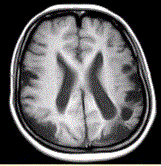

问题 女性,22岁。癫痫发作及智力异常。MRI显示见下图。 关于该病描述正确的是

选项 A.脑萎缩 B.双侧顶枕叶软化灶 C.蛛网膜囊肿 D.双侧顶枕叶脑梗死 E.脑积水 F.脑炎

答案 AB